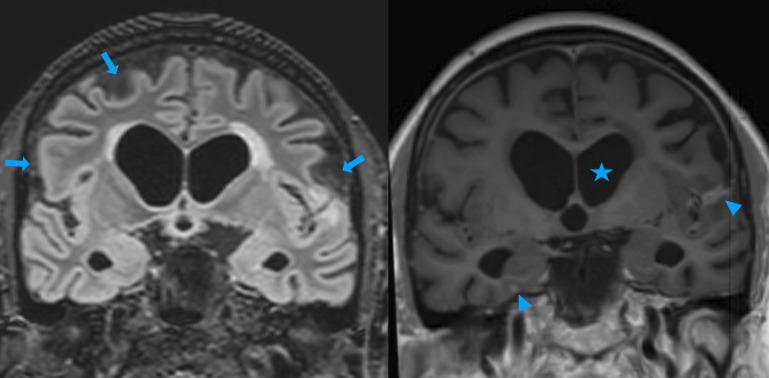

Cryptococcal meningitis is an important global health problem, resulting from infection with the yeast , especially and , which cause a spectrum of disease ranging from pulmonary and skin lesions to life-threatening central nervous system involvement. The diagnosis and management of cryptococcal meningitis have substantially changed in recent years. Cryptococcal meningitis often occurs in people living with advanced HIV infection, though in high-income countries with robust HIV detection and treatment programmes, it increasingly occurs in other groups, notably solid-organ transplant recipients, other immunosuppressed patients and even immunocompetent hosts. This review outlines the clinical presentation, management and prognosis of cryptococcal meningitis, including its salient differences in people living with HIV compared with HIV-negative patients. We discuss the importance of managing raised intracranial pressure and highlight the advantages of improved multidisciplinary team working involving neurologists, infectious disease specialists and neurosurgeons.

隐球菌性脑膜炎是一个重要的全球健康问题,由酵母感染引起,尤其是新型隐球菌和格特隐球菌,它们可导致一系列疾病,从肺部和皮肤病变到危及生命的中枢神经系统受累。近年来,隐球菌性脑膜炎的诊断和管理发生了重大变化。隐球菌性脑膜炎常发生于晚期HIV感染者中,不过在具备强大HIV检测和治疗项目的高收入国家,它越来越多地发生于其他人群,尤其是实体器官移植受者、其他免疫抑制患者甚至免疫功能正常的宿主。本综述概述了隐球菌性脑膜炎的临床表现、管理和预后,包括与HIV阴性患者相比,HIV感染者中的显著差异。我们讨论了控制颅内压升高的重要性,并强调了改善多学科团队协作(涉及神经科医生、传染病专家和神经外科医生)的优势。